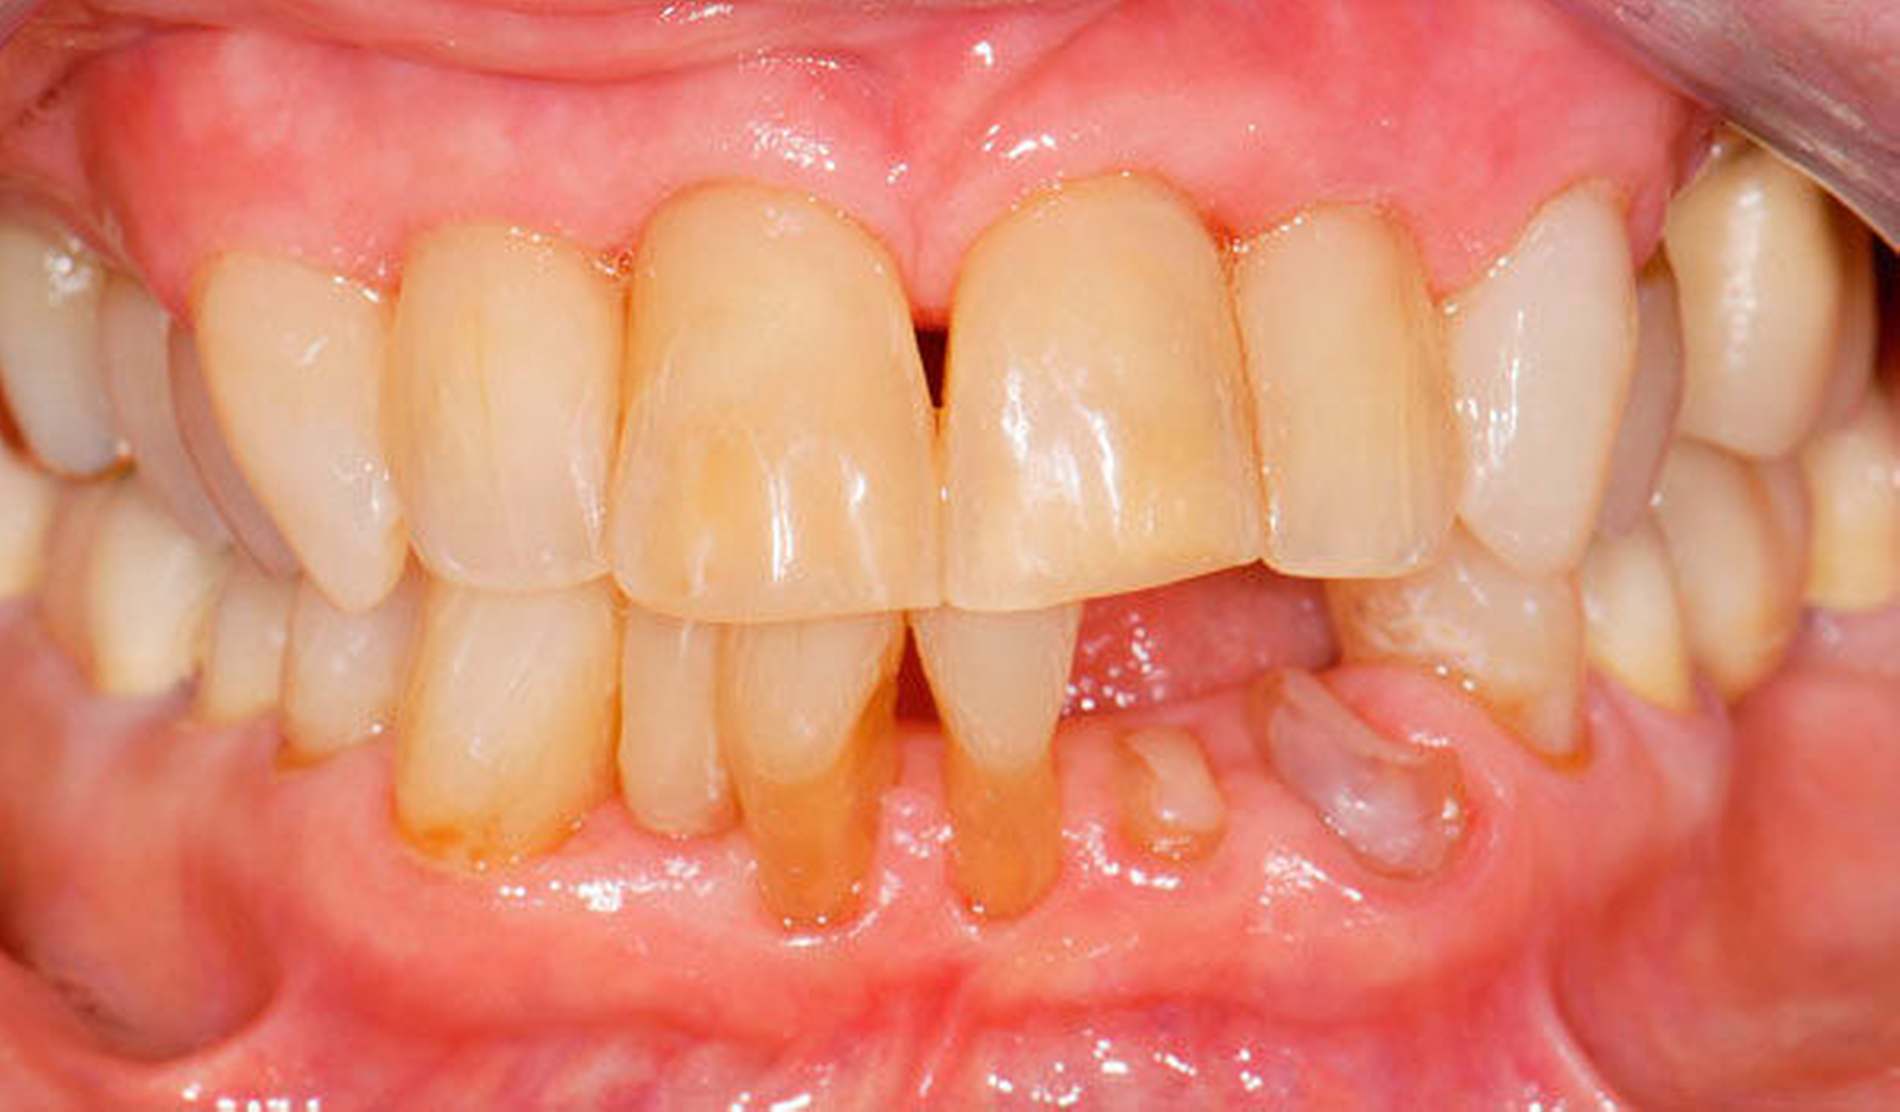

Abbildung 1 A-I: 84-jähriger Patient mit arterieller Verschlusskrankheit (Claudicatio intermittens)

Senioren haben – wie oben ausgeführt – immer häufiger zahlreiche eigene Zähne. Im Fall von Lückenbildungen müssen diverse Behandlungsalternativen in Erwägung gezogen werden. Dazu zählen neben klassischen prothetischen und implantologischen Versorgungen auch andere Optionen (Tabelle 1). Nicht jede Lücke muss geschlossen werden. Wenn funktionell und ästhetisch keine relevanten Einschränkungen bestehen, kann auch ein Monitoring (Belassen und Beobachten) eine gute Lösung sein [Staehle, 2010; Listl et al., 2016]. Daneben kommen zuweilen Zahnumformungen und -verbreiterungen (Abbildung 1) oder direkte Freiendanhänger aus Komposit als Behandlungsmittel zum Lückenschluss in Betracht [Staehle, 2007, 2009, 2010, 2012, 2017; Staehle et al., 2014, 2015a, b; Frese und Staehle, 2018]. Schließlich ist für Patienten, bei denen aufwendiger festsitzender Zahnersatz nicht möglich ist und die keine herausnehmbare prothetische Versorgung wünschen, die Verfolgung des Prinzips der verkürzten Zahnreihe [Walter, 2016] zuweilen eine gute Alternative. Zur praktischen Realisierung dieses Konzepts kann heute die konservierend-restaurative Zahnheilkunde (zum Beispiel über Zahnverbreiterungen und -anhänger, eventuell in Kombination mit Schienungen) ebenfalls viel beitragen.